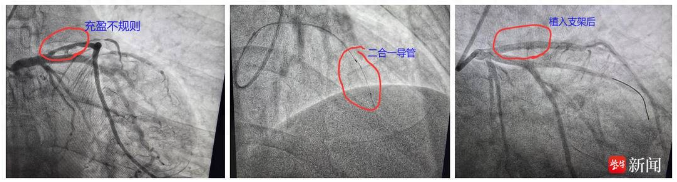

據(jù)悉,該患者為一外地男性,61歲,反復(fù)活動(dòng)后胸悶氣喘,因外地冠脈造影未能處理慕名至鎮(zhèn)江瑞康醫(yī)院就診。該院心內(nèi)科團(tuán)隊(duì)為患者制定了精準(zhǔn)的診療方案,造影發(fā)現(xiàn)患者前降支近段不規(guī)則造影劑充盈,60%%狹窄(未達(dá)到支架植入標(biāo)準(zhǔn))。

內(nèi)膜撕裂

為進(jìn)一步明確該病變是否穩(wěn)定,是否需要干預(yù),瑞康醫(yī)院心內(nèi)科團(tuán)隊(duì)討論后決定行IVUS(聲)和OCT(光)二合一導(dǎo)管進(jìn)一步檢測(cè)。結(jié)果發(fā)現(xiàn)血管內(nèi)膜撕裂明顯,植入支架一枚,成功并完美解決患者的病痛。